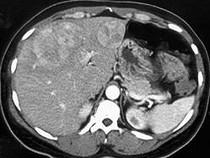

女,65岁,肝区疼痛1月余,CT检查如图,最可能的诊断是()A.原发性肝癌B.类癌转移至肝C.肝腺瘤D.肝血管瘤E.肝错构瘤

问题 女,65岁,肝区疼痛1月余,CT检查如图,最可能的诊断是()

选项 A.原发性肝癌 B.类癌转移至肝 C.肝腺瘤 D.肝血管瘤 E.肝错构瘤

答案 B